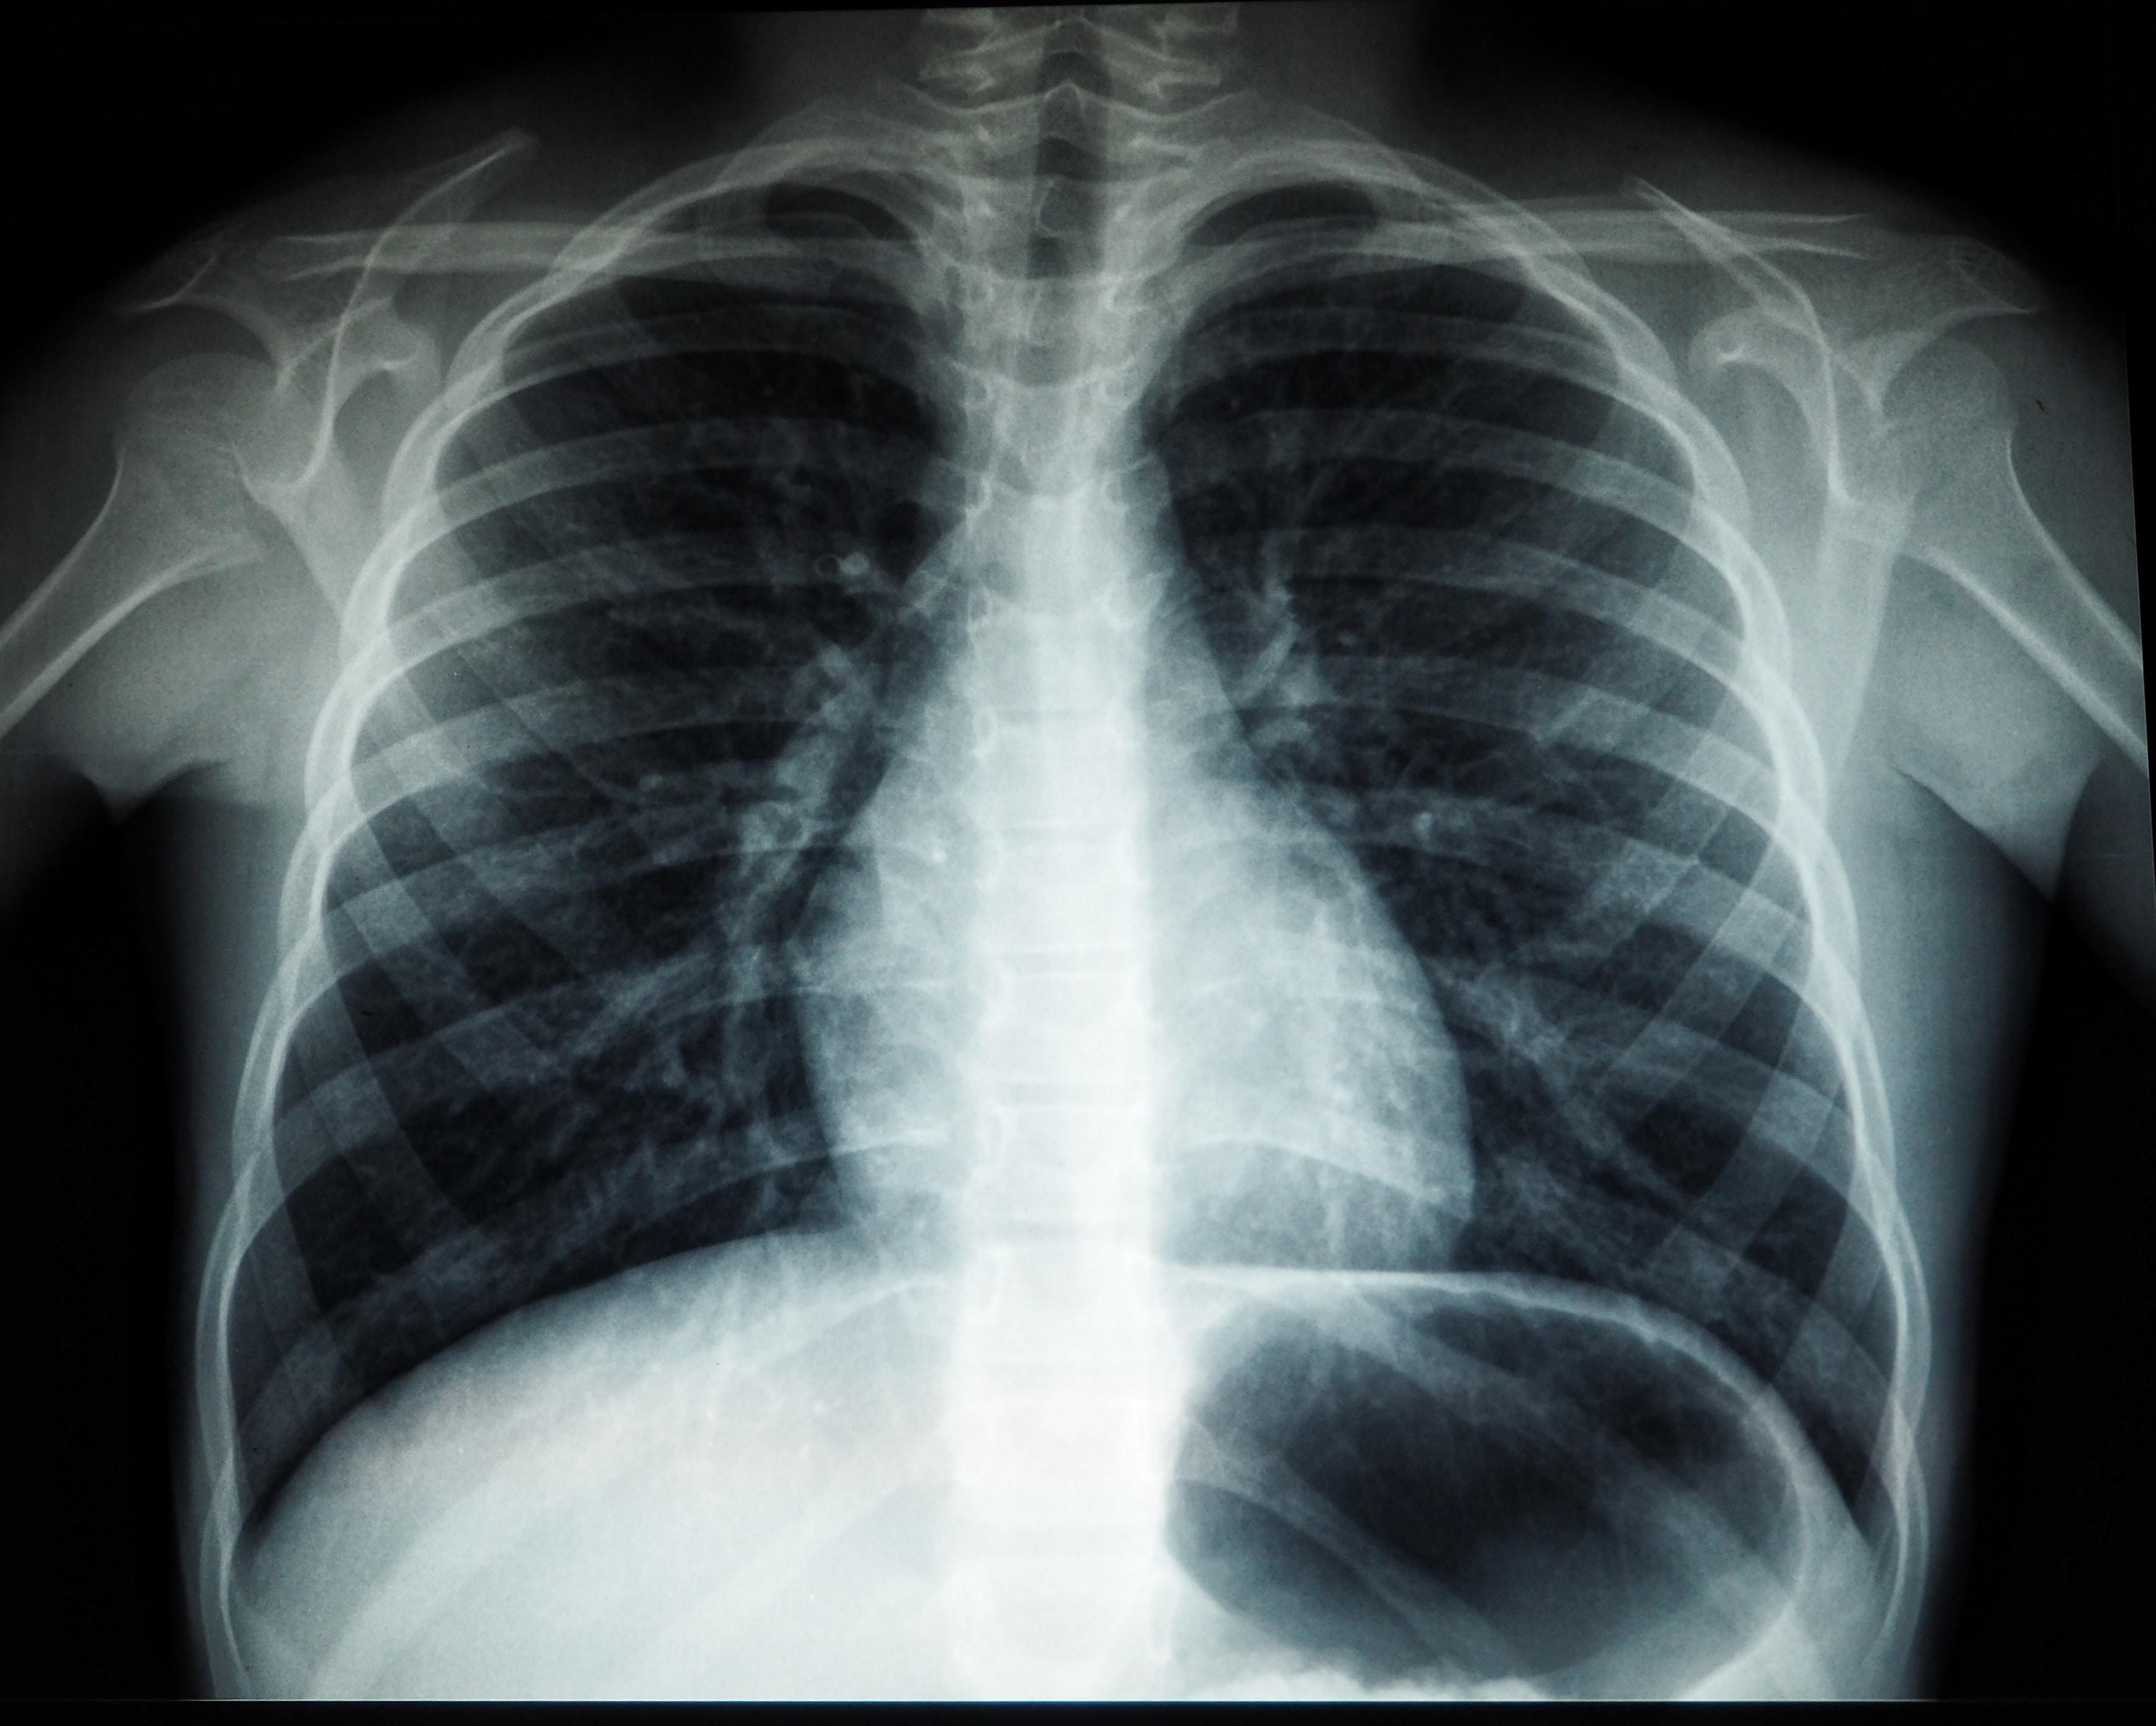

咳嗽超過兩周就應該盡早進行X光檢查。

如果咳嗽持續兩星期,屬不正常狀況,除發炎外,亦可能由肺癌或肺結核引起,如X光結果呈現白點或「空洞」,可能為肺結核,肺結核的初期症狀不明顯,很多時被誤認為感冒,症狀包括嚴重咳嗽、咳痰、虛弱、疲勞及體重減輕等;如出現小腫瘤,則可能為是由肺癌引起。